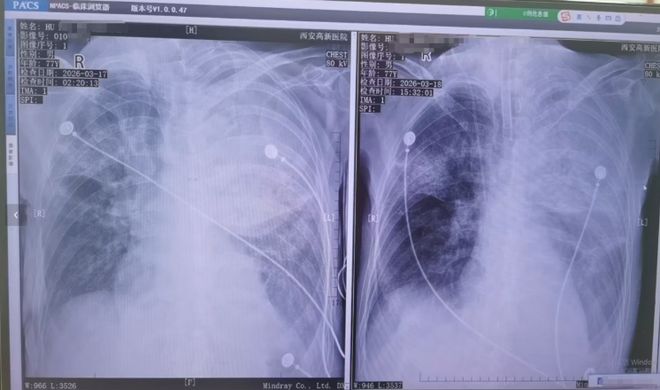

当初医生诊断为普通的感冒,并没有发现其他严重的问题,但随后病情迅速恶化,肺部出现大面积炎症。3月17日父亲被紧急转院至西安高新医院进行抢救,经检查确认是由鹦鹉热衣原体感染引起的重症肺炎及其他并发症。胡先生提供了医院开具的诊断证明。

患者接受转院治疗

患者胸片